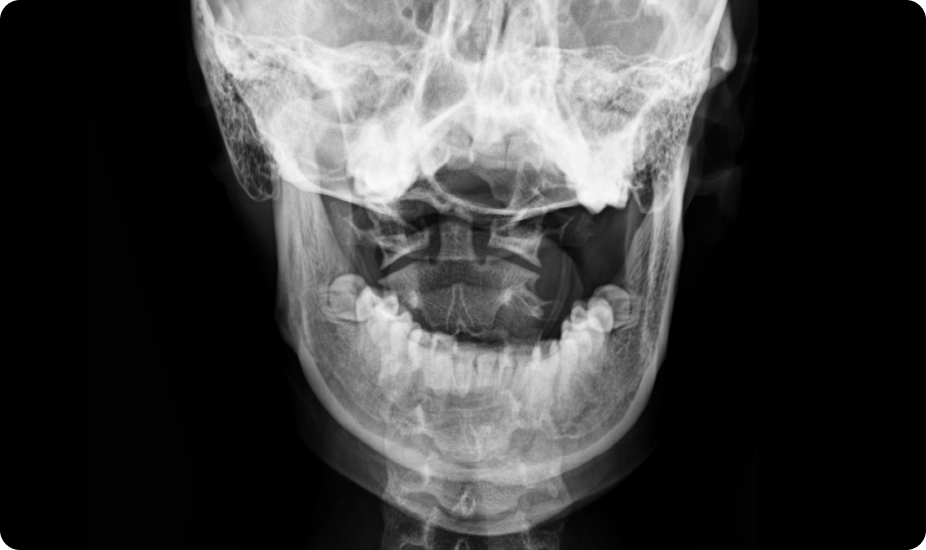

턱관절 장애를 동반한 성장부진

턱관절의 비대칭이나 불균형은 경추 1, 2번의 틀어짐과 두개골의 비대칭을 유발하여 뇌하수체에서 분비되는 성장 호르몬과 성호르몬에 영향을 줄 수 있습니다.

턱관절 부정교합 턱관절 및 상부경추교정 (성장호르몬 전달기능 개선)

상부경추 틀어짐

턱 위치를 바로잡아 접형골의 틀어짐을 교정, 뇌하수체 기능향상을 통해 성장 호르몬 분비 촉진